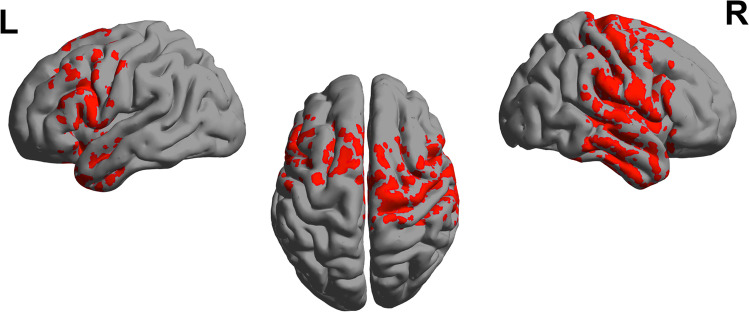

An overview of the results obtained is provided in Table 1, as specifically shown in Fig 2 resting state EEG showed significant increases in spectral power for CUD patients compared with controls across all four frequency bands, albeit this effect was most distributed in the alpha band (Fig 2). To improve specificity, we tested for differences in relative (%) power, often used to normalize spectra under a constant value of broadband (1-40 Hz) power, and reflecting the degree of spectral slowing (i.e., greater relative power in lower frequencies) or spectral acceleration (i.e., greater relative power in higher frequencies). As shown in Fig. 2, patients demonstrated regions of anatomically selective excess of slow-waves amplitude (alpha), in line with previous research (Kalivas & O’Brien, ref. 2008). Specifically, relative alpha power was significantly more elevated in the cortex of patients relative compared with controls (Fig 3), with a statistical threshold of p < 0.05 at a t-values of t >1.67.

CUD was associated with relative alpha power increases within frontocentral regions, with a maximum in the sensorimotor cortex (t = 2.11, p < 0.05). On the other hand, relative theta and beta power were reduced within the temporal lobe (t = −1.99, p < 0.05; t = −1.87, p < 0.05 respectively). No significant differences were found in the delta band.

The present study focused on the relationship between alpha oscillations and attention in adult cannabis users, using an experimental design with resting EEG and behavioral task conditions. By examining the cortical dynamics of CUD patients using EEG signals, and calculating spectral power profiles, our results indicate that: 1) CUD patients showed increased alpha power over frontal regions compared to controls, and 2) their attentional performance (hit accuracy) inversely correlates with individual levels of frontal alpha power in the sensorimotor cortex (Table 1).

Specifically, in our study, patients’ cortical activation was reduced compared with control subjects, given that they exhibited an increase in slow-wave alpha power, peaking over the sensorimotor regions (p < 0.05). This excess of alpha rhythmicity may be associated with cortical inhibition or reduced information processing (Klimesch, ref. 1999), and its location in frontal regions might be responsible for attentional impairments.